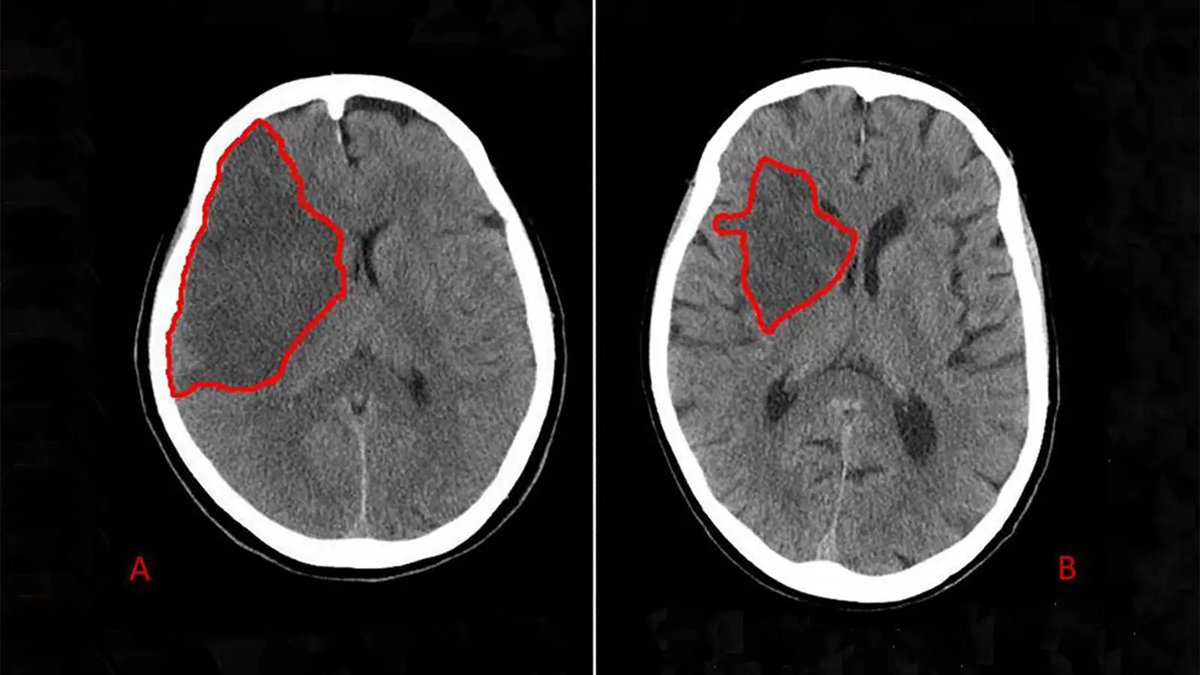

الحرف الثالث هو ال “B”

ونقصد فيه الBrain

لازم نتأكد من عدم وجود:

1) Midline shift / herniation

2) loss of Grey-white matter differentiation

وحدة من علامات الستروك "early sign”

3)brain atrophy

4)Hypo/hyper dense areas